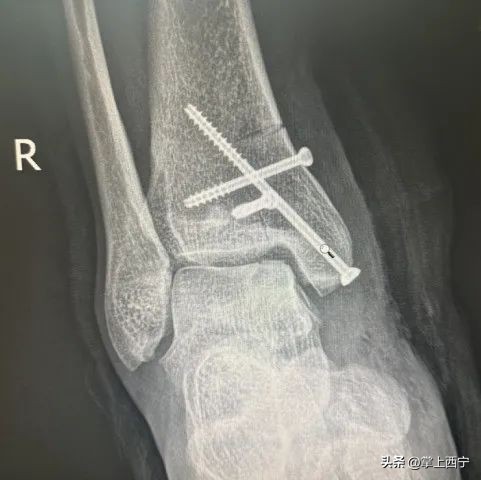

↑ 术后X射线平片

术后第三天查房时张大伯表示,现在疼痛明显减轻很多,没想到这么复杂的手术竟然这么顺利,术前紧锁的眉头终于舒展了。经过手术治疗,踝关节疼痛较前明显减轻,在骨愈合后逐步功能锻炼会得到良好效果。